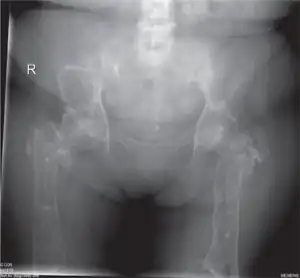

- Osteoporosis: 75% of patients develop visible bony abnormalities due to the accumulated glucosylceramide. A deformity of the distal femur in the shape of an Erlenmeyer flask is commonly described.